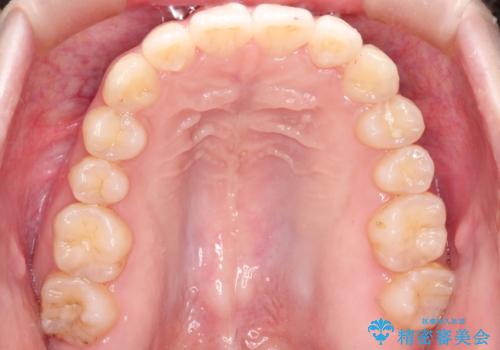

前歯にがたつきがあり、上下の歯が咬み合っていない状態でした。

歯列の横幅をひろげるのと、歯と歯の間をわずかに削ることにより、前歯のがたつきと、開咬を改善しました。